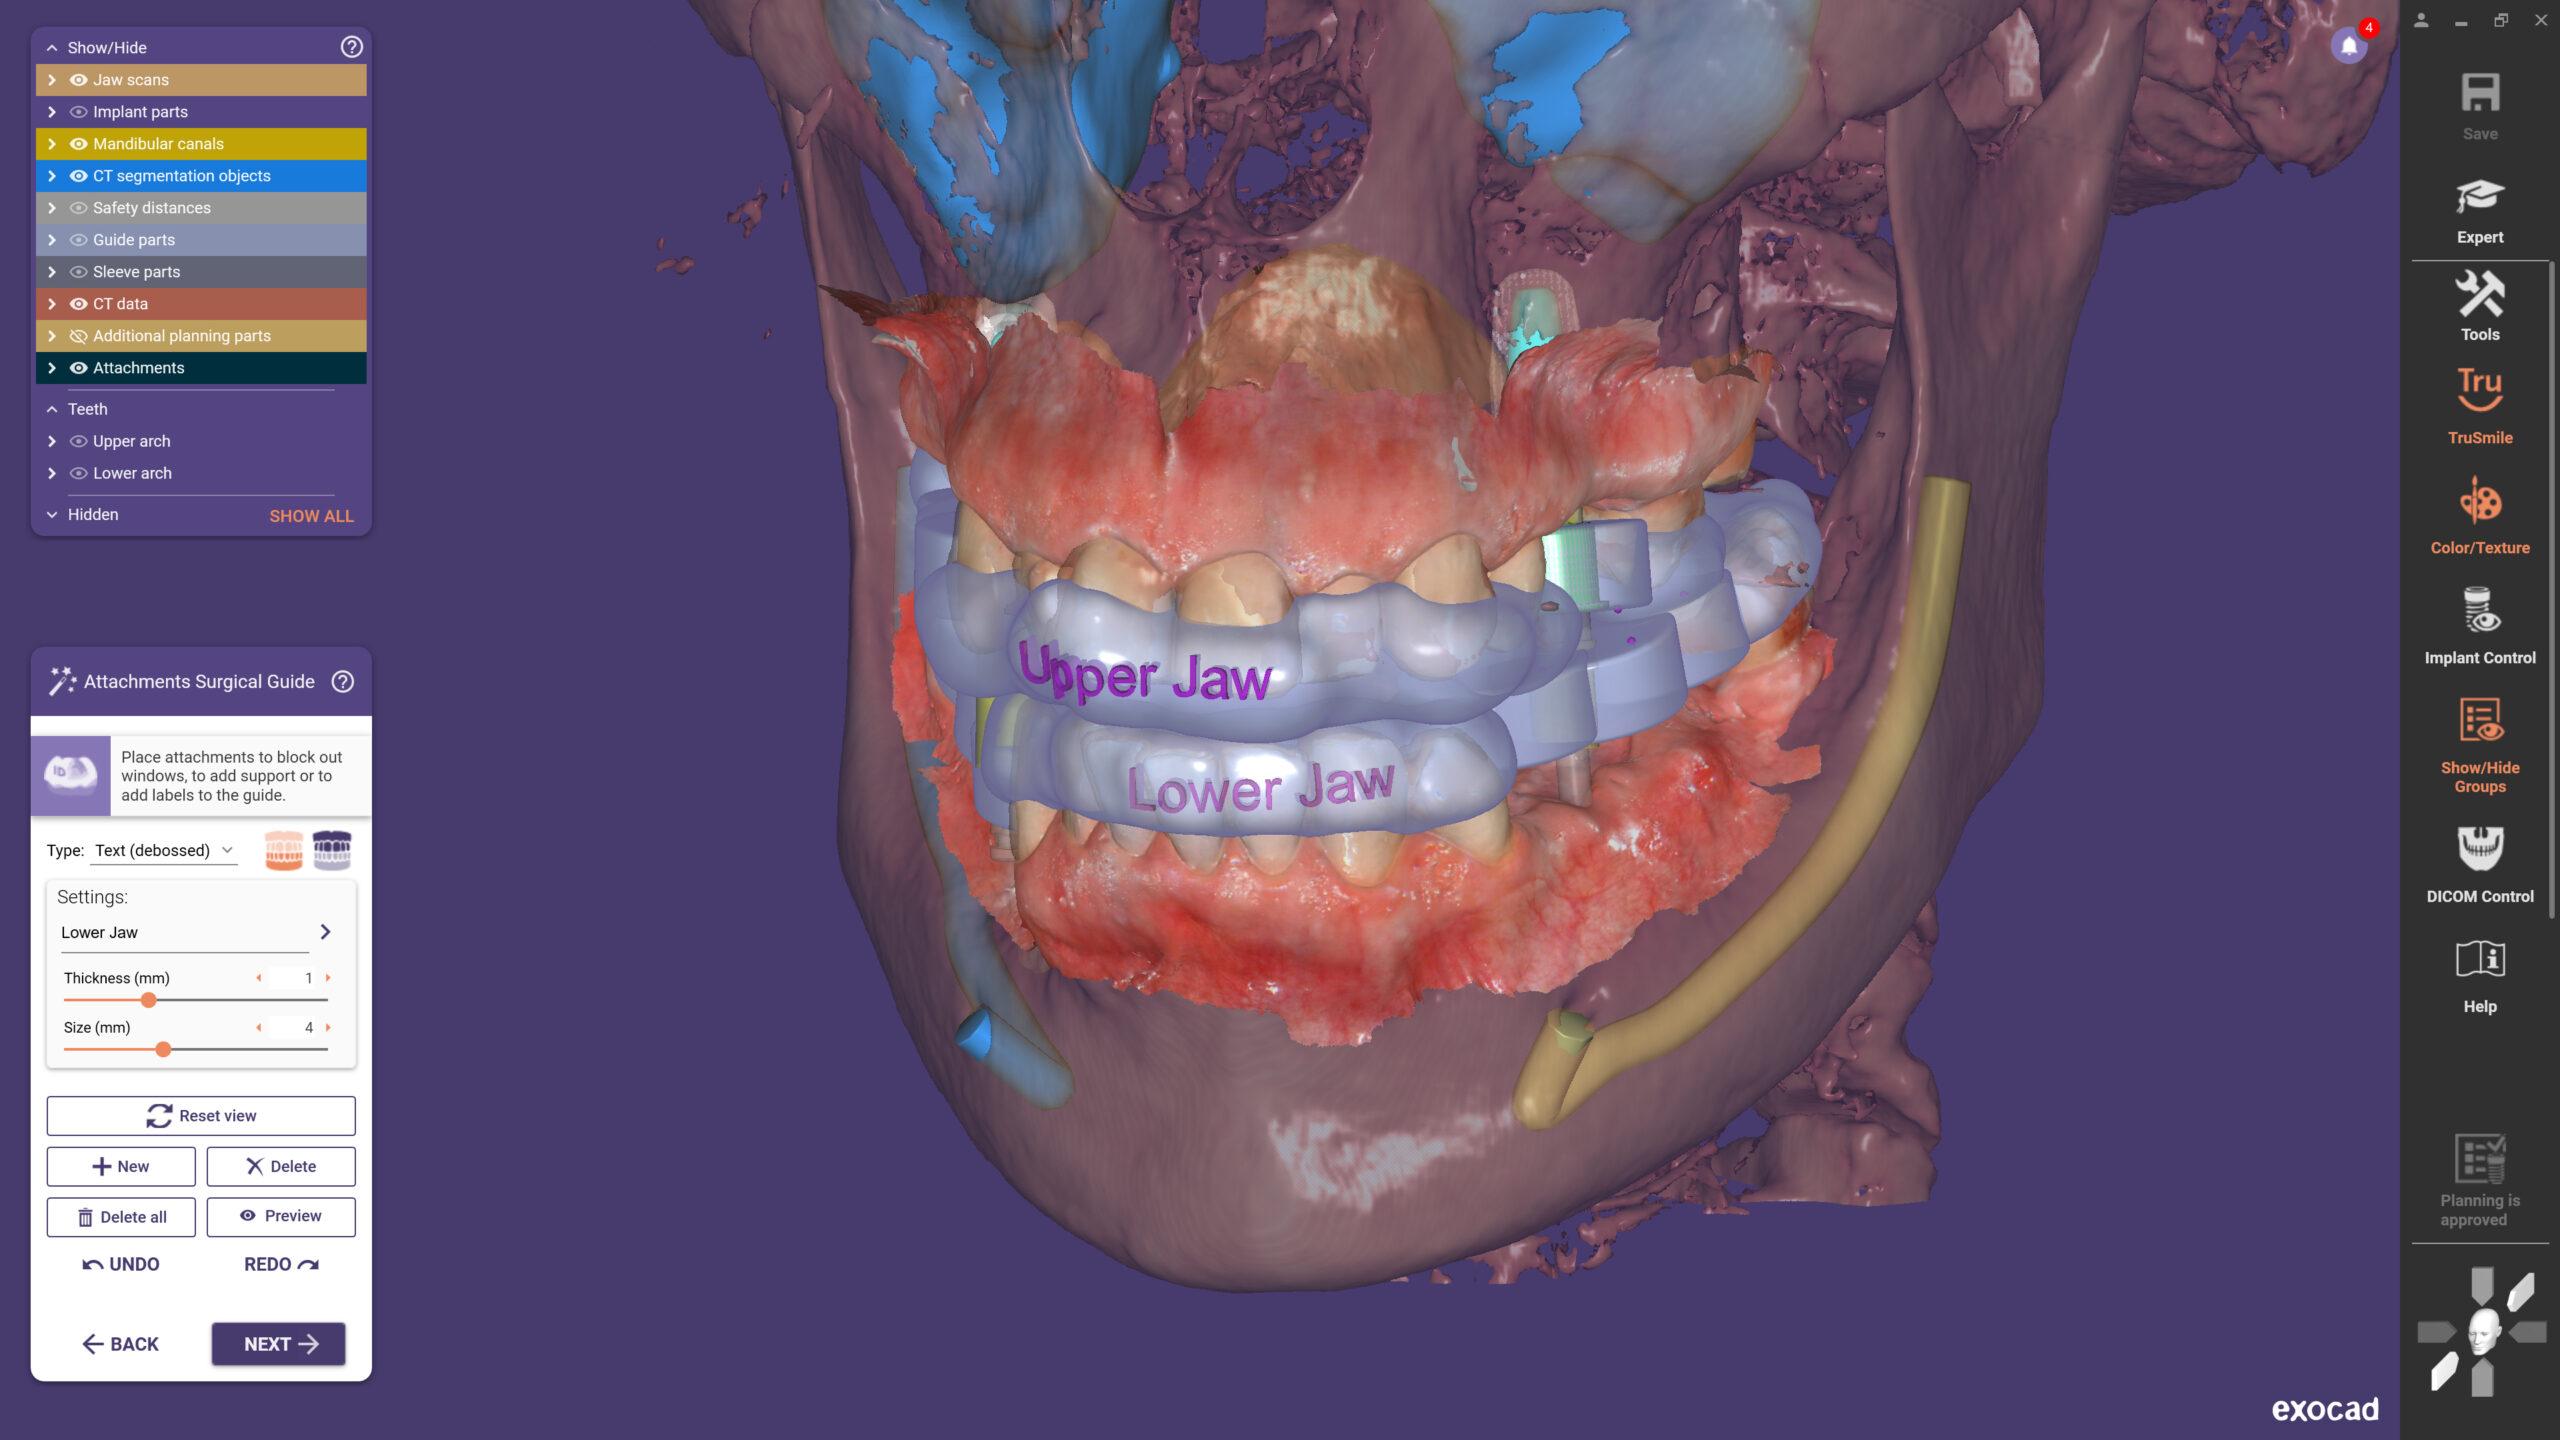

Exoplan je preoperativni softver koji se koristi za digitalno planiranje pozicije, veličine i orijentacije dentalnih implantata. Omogućava integraciju CBCT snimaka, intraoralnih i ekstraoralnih skenova, čime se dobija trodimenzionalni prikaz kosti, zuba i važnih anatomskih struktura. Na ovaj način, stomatolog dobija jasnu i realističnu sliku situacije prije same operacije.

- Planiranje i proizvodnja hirurških vodilica – uz modul Guide Creator, moguće je interno dizajnirati i 3D printati vodilice, što donosi značajnu uštedu vremena i troškova.

Sve veći broj stomatologa prelazi na digitalne tehnologije, a implantologija je jedno od područja gdje su prednosti najizraženije. Exoplan omogućava „crown-down“ planiranje – kreiranje protetskog rada i na osnovu njega pozicioniranje implantata. Time se osigurava funkcionalnost i estetika konačnog rada, a pacijenti dobijaju predvidive i dugoročno uspješne rezultate.